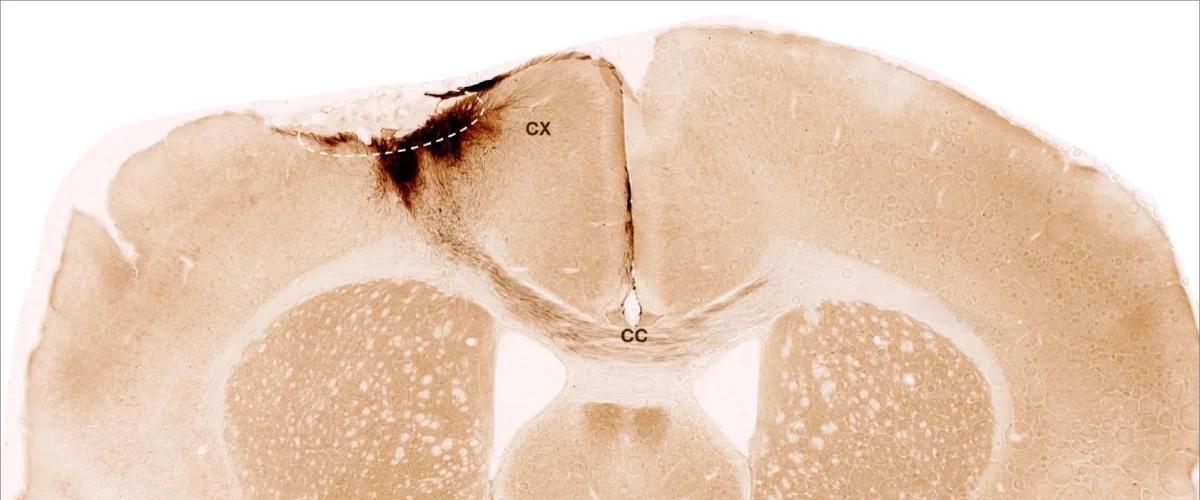

Новое экспериментальное лечение с применением стволовых клеток провели ученые из Цюрихского университета. Для лечения мышей после инсульта они использовали стволовые клетки человека, которые могут преобразовываться в различные типы клеток нервной системы.

Клетки вводили через неделю после инсульта. В течение пяти недель наблюдений ученые отметили полную выживаемость этих клеток, а также преобразование большинства из них в новые нейроны. Помимо новых нейроны, которые успешно взаимодействовали с другими клетками, ученые отметили основные признаки запуска регенерации ткани.

Например, отмечен рост новых кровеносных сосудов, снижение воспаления, а также повышение целостности гематоэнцефалического барьера. Особенно важно, что лечение обратило вспять двигательные нарушения после инсульта.